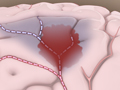

If you have serious blockage in the carotid arteries in your neck, you may need a carotid endarterectomy. During this surgery, a surgeon removes plaque buildup in the carotid arteries. The benefits and risks of this surgery must be carefully weighed, because the surgery itself may cause a stroke.

Carotid artery stenting (also called carotid angioplasty and stenting) is sometimes done as an alternative to surgery to prevent a transient ischemic attack (TIA) or stroke.

In this procedure, a doctor threads a thin tube called a catheter through an artery in the groin and up to the carotid artery in your neck. The doctor then uses a tiny balloon to enlarge the narrowed portion of the artery and places a stent to keep the artery open.

Carotid artery stenting is not as common as carotid endarterectomy, a type of surgery.